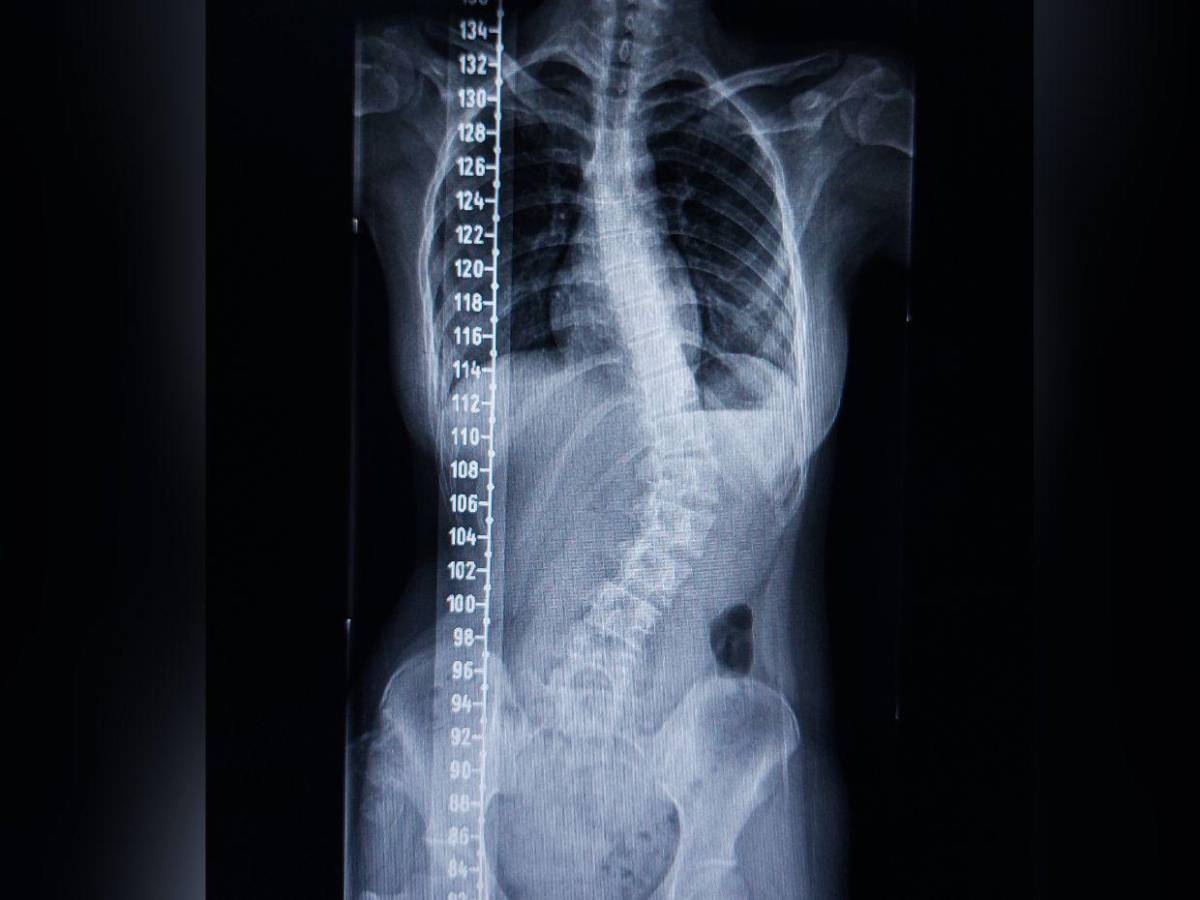

La escoliosis también está entre los problemas más destacables de la espalda. Puede pasar desapercibida porque no siempre da síntomas o estos pueden ser leves.

“La escoliosis es una curvatura anormal de la columna vertebral. Imagínate la columna como una línea recta que conecta la cabeza con la pelvis. Pues bien, cuando una persona tiene escoliosis, esa línea recta se curva hacia los lados, como si fuera una S o una C. Suele ocurrir en la adolescencia, aunque puede desarrollarse en cualquier momento de la vida”, subraya.